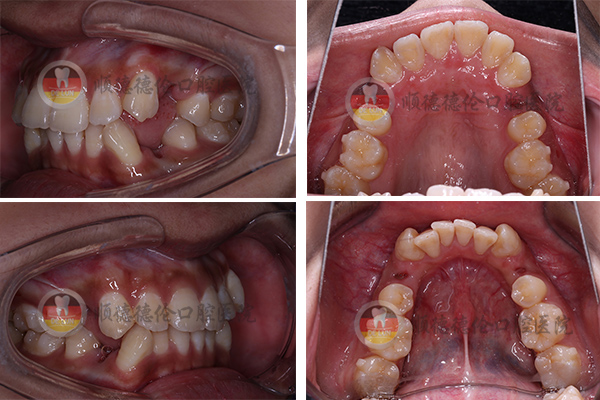

牙齒狀況:牙齒外突、擁擠、不整齊

3、拍口內(nèi)照

上下兩排牙齒共拔了8顆牙齒,為了變美我也是拼了(⊙o⊙)

我的方案是要拔牙的,說(shuō)出來(lái)估計(jì)會(huì)嚇到別人,因?yàn)槲野瘟?顆,分三次拔完了,估計(jì)很少有人能夠理解,周?chē)簧倥笥颜f(shuō)我瘋了,我是想美想瘋了,哈哈哈……